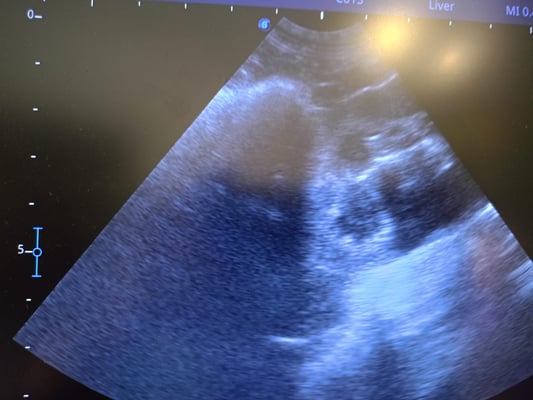

Doch dann erkannte unsere liebe Grig endlich die Ursache für ihren schlechten Zustand: Das arme Mädchen war voller Herzwürmer! Ein Röntgenbild und eine Ultraschallaufnahme zeigten das wahre Ausmaß der Situation.

But then our dear Grig finally recognized the cause of her terrible condition: the poor girl was full of heartworms! An x-ray and an ultrasound showed the true extent of the situation.